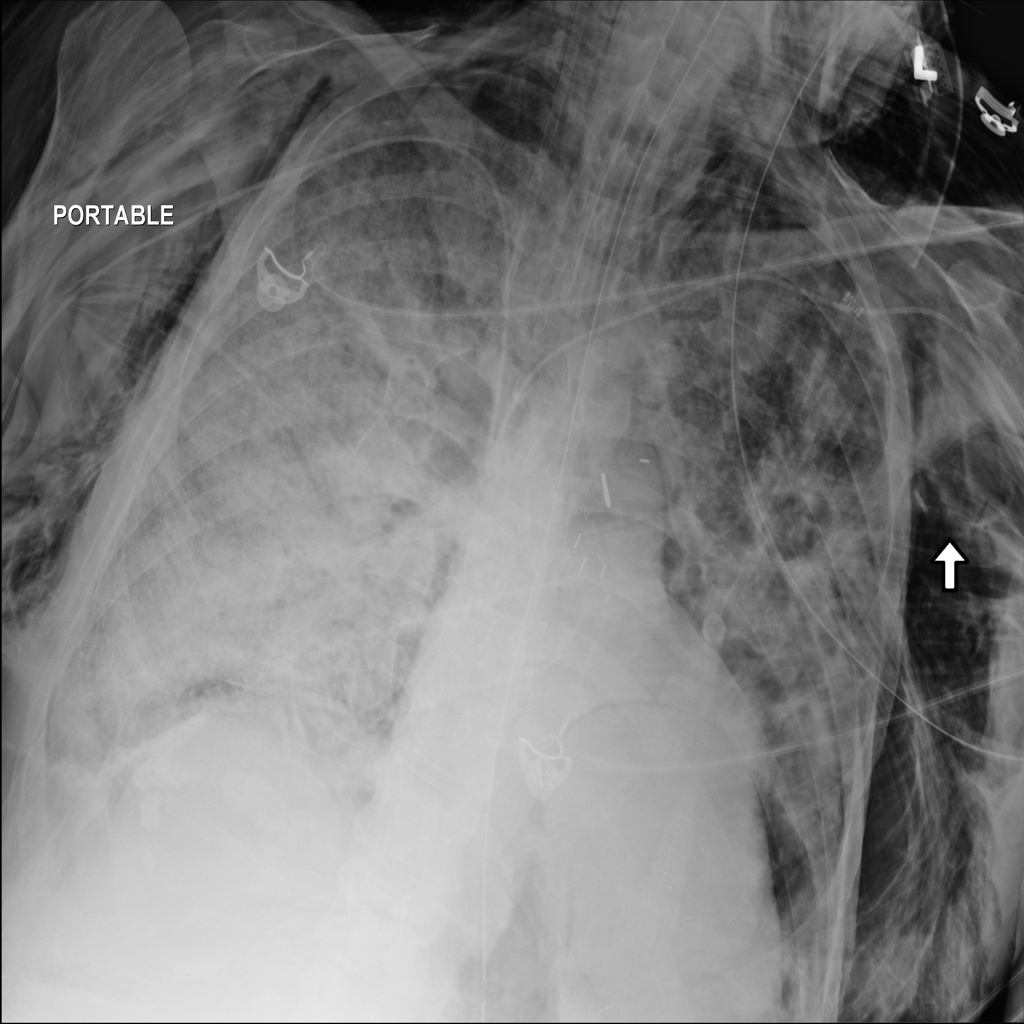

PAT-4639 · IMG-020Pneumothorax

PAT-4639 · IMG-020

PA